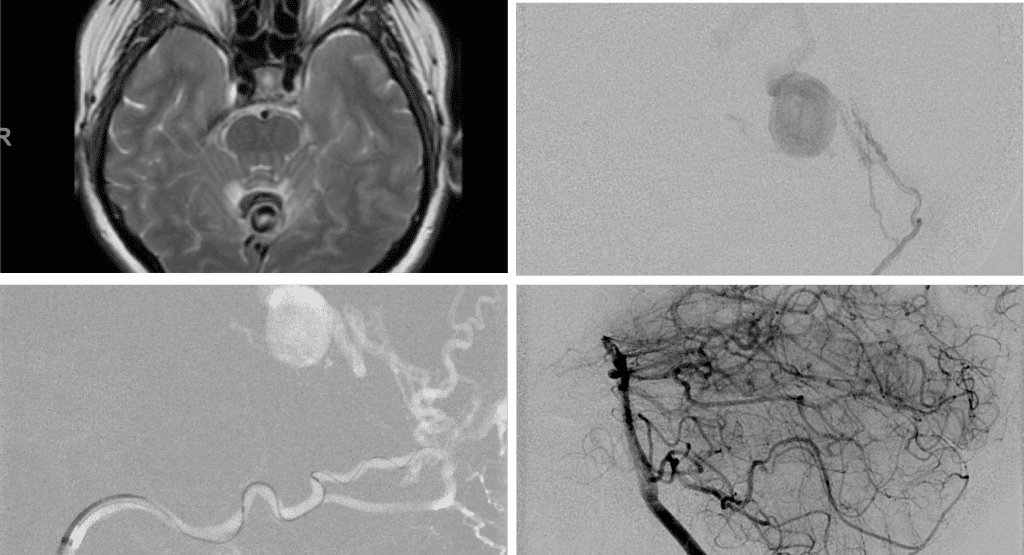

Figure 3. Right ECA AP and Lateral angiograms Pre (A and B) and Post NBCA embolization (C and D) Demonstrate near complete obliteration of right Occipital and Middle Meningeal Artery Fistulas

Figure 4. Left ECA AP and Lateral angiograms Pre (A and B) and Post NBCA embolization (C and D) Demonstrate near complete obliteration of Left Occipital Artery Fistulas.

Embolization was successful at immediately reducing the pressure into the Aneurysmal Varix with greater than 90% reduction in A-V shunts. After an intensive period of critical care monitoring and care for her initial brain hemorrhage, she made a near complete recovery with mild intermittent left sided paresthesias and generalized deconditioning. After receiving inpatient and outpatient Acute Rehabilitation, Physical, and Occupational therapy, she completely recovered all of her Activities of Daily Living (ADLs) at 3 months and achieved an modified Rankin Scale (mRS) of 0. On follow-up angiography, small residual low flow A-V shunts were identified and targeted for Gamma Knife Radiosurgery (Figure 5 and 6).